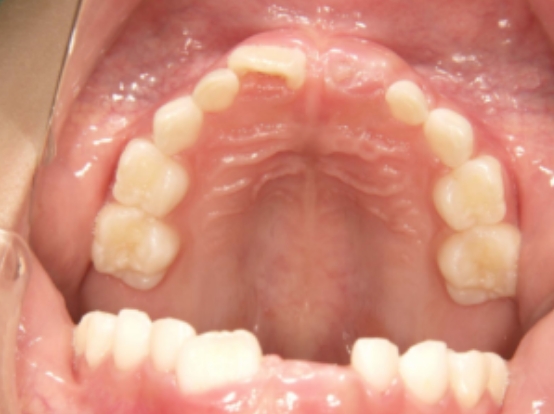

治療前① 小1:初診

治療スタート:7y4m

9y7m:ベロ機能の練習前

上の歯列弓の中に納まらない状態